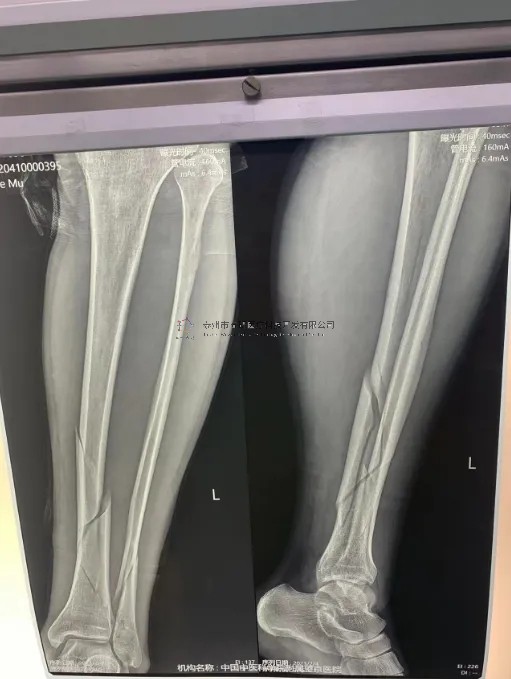

2月份,我們?cè)谥袊?guó)中醫(yī)科學(xué)院望京醫(yī)院就有多臺(tái)關(guān)于外固定支架的手術(shù),以下介紹一則不開刀CO接骨治療小腿骨折典型病例:

【所屬科室】創(chuàng)一

【基本資料】患者,男,43歲

【患者情況】左脛腓骨近端骨折

【影像圖片】